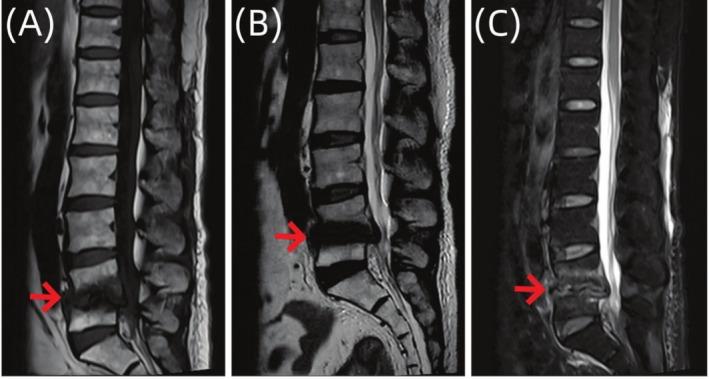

Suppurative Spondylitis Misdiagnosed as Endplate Inflammation: A Rare Case Report.

Spinal infectious diseases are difficult to diagnose and treat; we reported a case of pyogenic spondylitis misdiagnosed as terminal discitis and successfully treated. The application of metagenomic next-generation sequencing technology holds promise in greatly improving diagnostic efficiency.